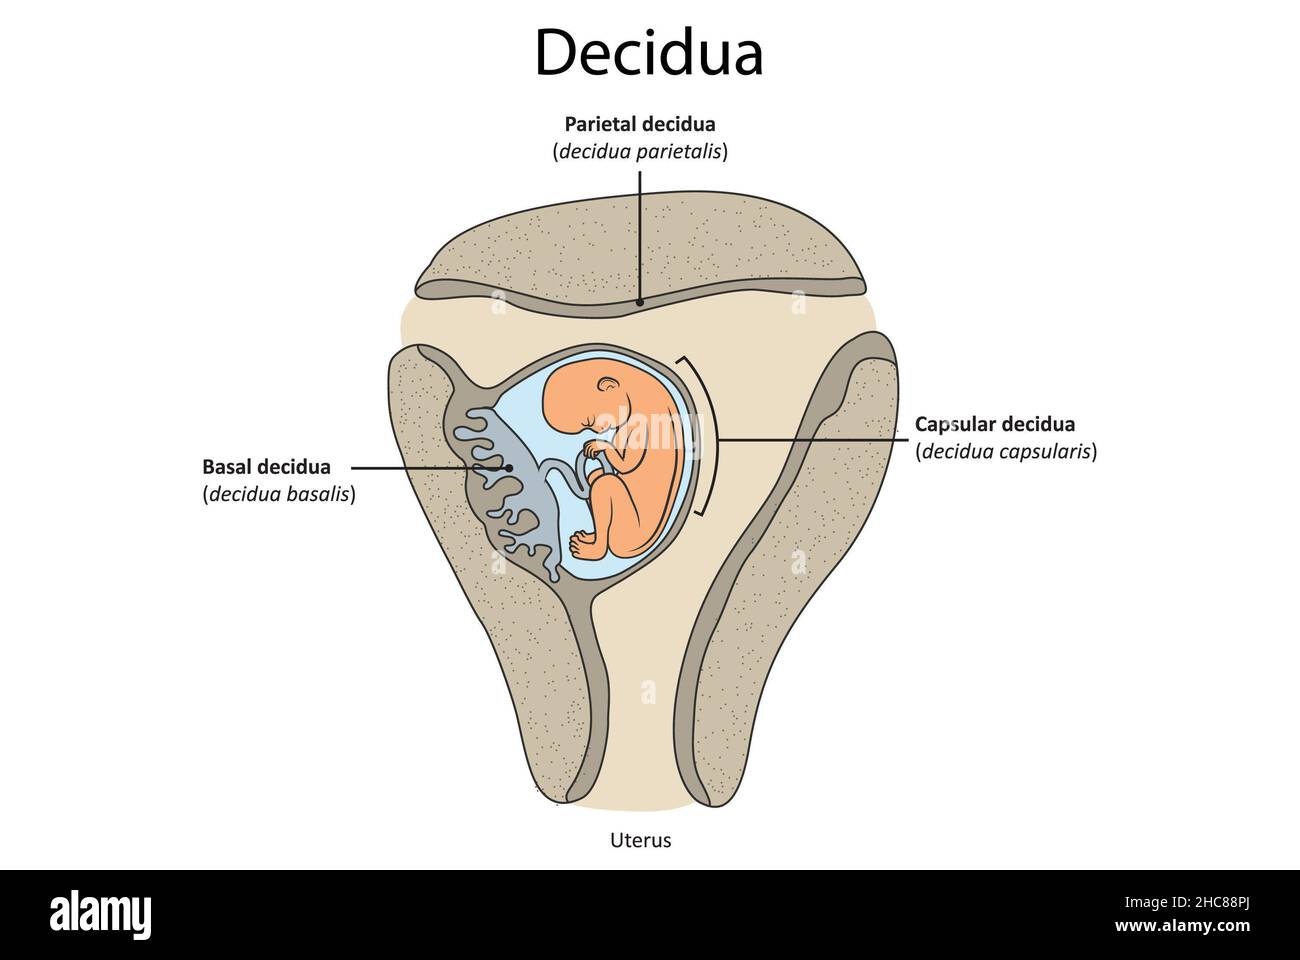

A. The Decidua

The decidua has three separate areas:

Decidua basalis, the part of the endometrium that lies directly under the embryo (or the portion where the trophoblast cells establish communication with maternal blood vessels)

Decidua capsularis, the portion of the endometrium that stretches or encapsulates the surface of the trophoblast

Decidua vera/parietalis, the remaining portion of the uterine lining. As the embryo continues to grow, it pushes the decidua capsularis before it like a blanket. Eventually, the embryo enlarges so much that this action brings the decidua capsularis into contact with the opposite uterine wall (the decidua vera). Here, the two decidua areas fuse, which is why, at birth, the entire inner surface of the uterus is stripped away, leaving the organ highly susceptible to hemorrhage and infection